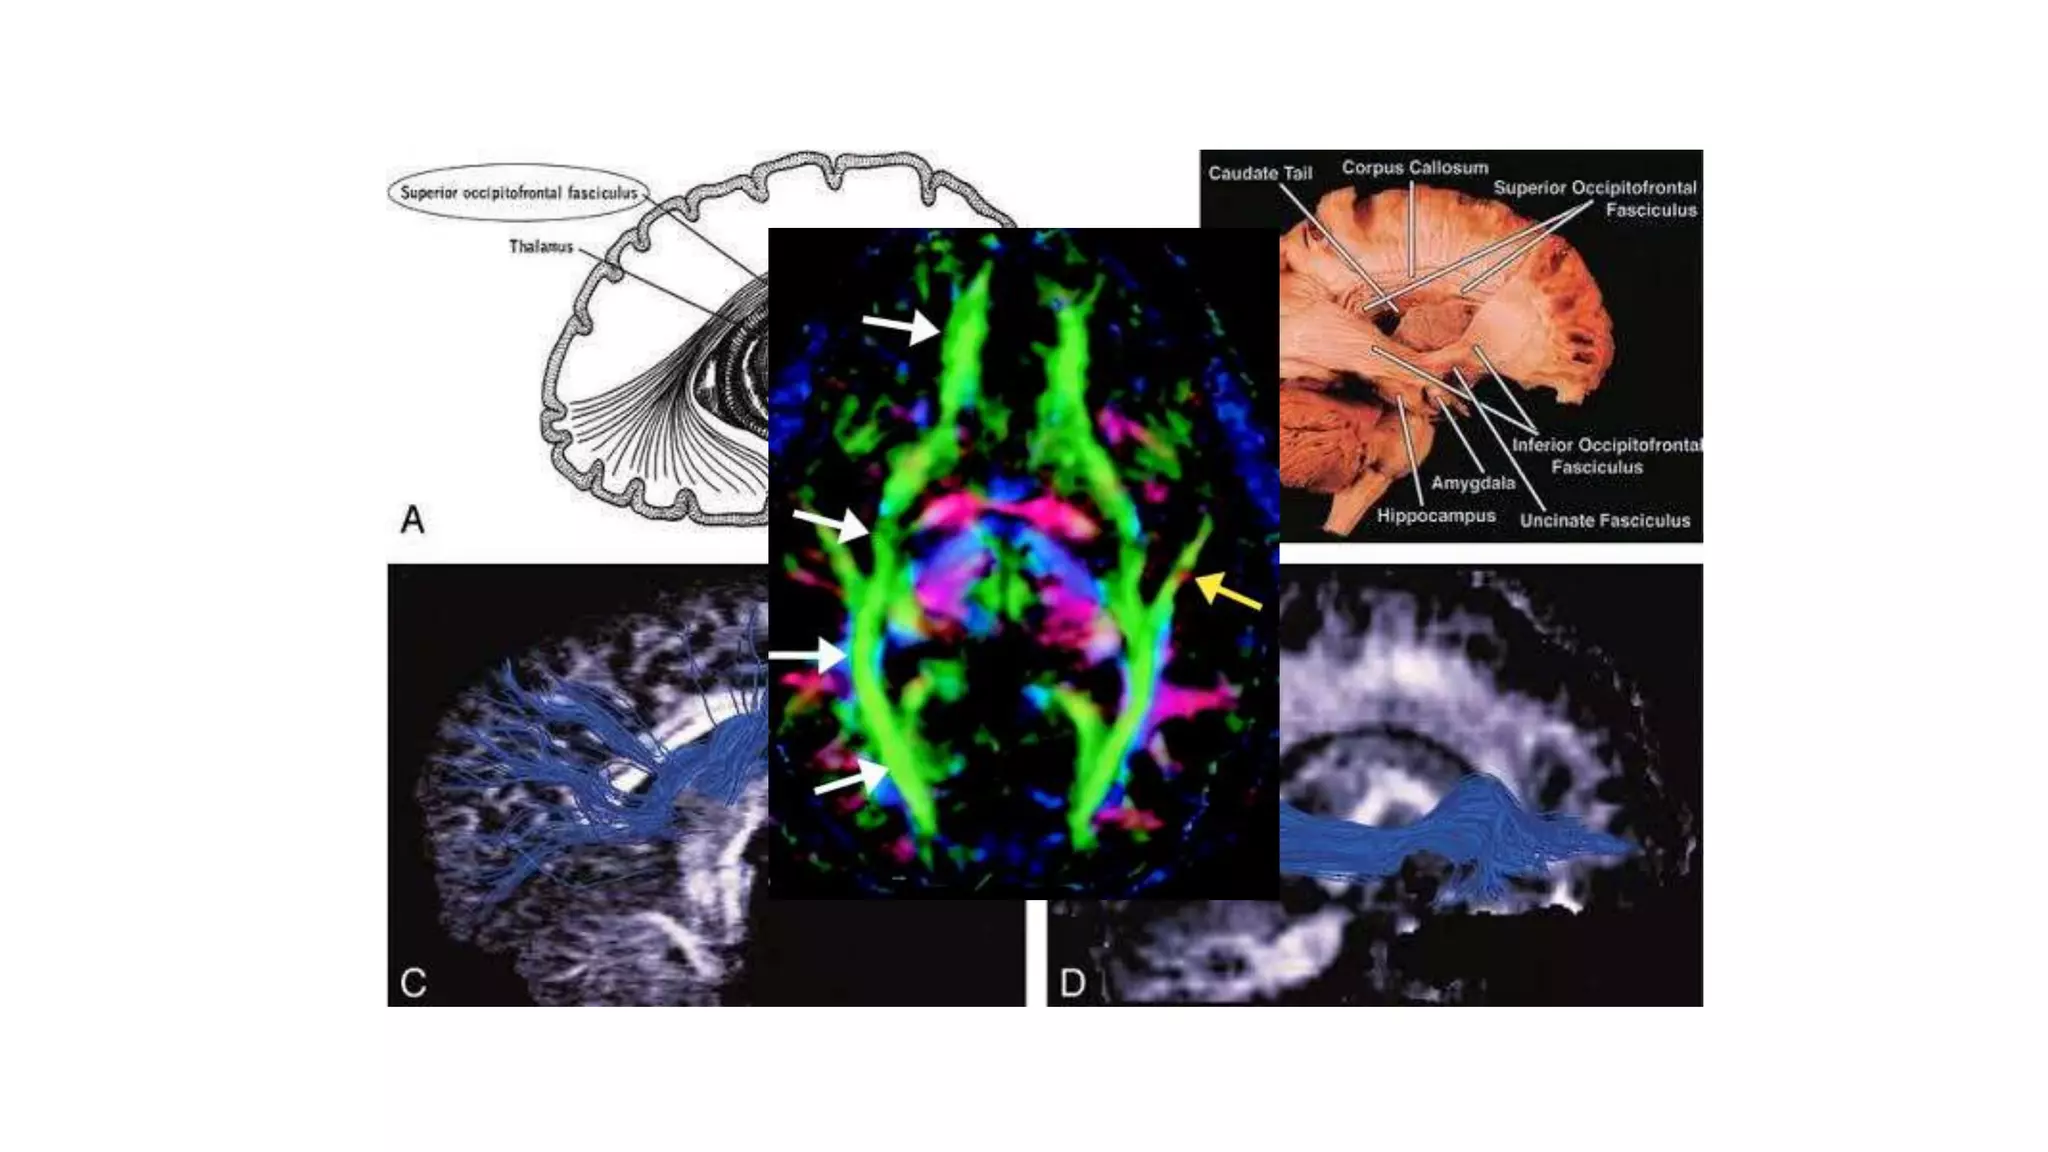

Superior occipito-frontal fasciculus

It lies beneath the corpus callosum

It connects occipital and frontal lobes,

extending posteriorly along the dorsal

border of caudate nucleus.

Some part of it parallel to superior

longitudinal fasciculus but separated from

it by corona radiata and internal capsule

Uncinate fasciculus

 It connects parts of the limbic system such as

temporal pole, anterior para-hippocampus and

amygdala

 Hook shaped bundle which links anterior temporal

lobe with orbital & inferior frontal gyrus of the

frontal lobe

Superior occipito-frontal fasciculus Itlies beneath the corpus callosum It connects occipital and frontal lobes, extending posteriorly along the dorsal border of caudate nucleus. Some part of it parallel to superior longitudinal fasciculus but separated from it by corona radiata and internal capsule  It also connects the occipital and frontal lobe but is far inferior than superior occipitofrontal fasciculus  Extend along the inferolateral edge of the claustrum, below the insula Inferior occipito-frontal fasciculus

• #28 Superior and inferior occipitofrontal fasciculi sagittal view.A, Illustration shows the superior occipitofrontal fasciculus hooking around the lateral sulcus to connect arching over the caudate nucleus to connect frontal and occipital lobes, and the inferior frontal and anterior temporal lobes. B, Gross dissection, lateral view. Like the superior occipitofrontal fasciculus, the inferior occipitofrontal fasciculus connects the frontal and occipital lobes, but it lies more caudal, running inferolateral to the claustrum.C and D, Tractograms of the superior (C) and inferior (D) occipitofrontal fasciculi. Axial directional map showing IOFF That lies in a roughly axial plane and is easily identified in green; it connects frontal and occipital lobes at the level of the midbrain.

• #30 Illustration shows the uncinate fasciculus hooks around the lateral sulcus to connect inferior frontal and anterior temporal lobes. B, Tractogram.